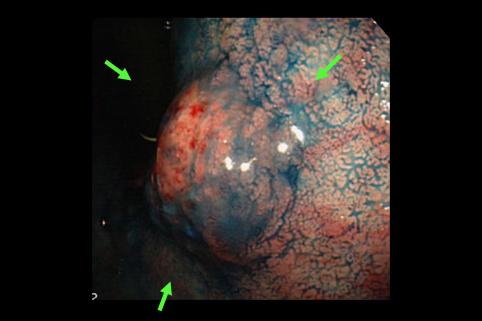

A case of type 0-I early gastric cancer which was histologically mucinous adenocarcinoma and showed a submucosal tumor like appearance.

[Image-ID:11420]

악성 상피성종양/점액암

위(부위)/체부

0형(표재형)/I형(I)

25~29

sm